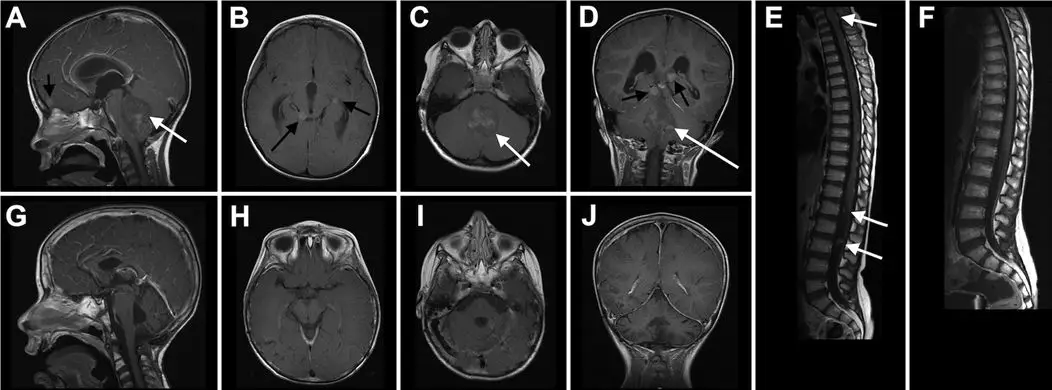

颅内蛛网膜囊肿(AC)常常是在评估脑外伤、癫痫和发育迟缓时行影像学检查偶然发现的,儿童AC的发病率大约2.6%,成人AC的发病率为1.1%到2.3%,提示部分AC可自行消失。颞叶AC最常见,按照Galassi分型分以下三型:I型囊肿(局限于中颅窝,呈梭形),II型(体积中等,呈三角或四边形,占据中颅窝前中部,沿侧裂生长),III型(体积巨大,卵圆形或圆形,充满整个中颅窝,可向大脑半球生长波及多个脑叶)。I型囊肿不需治疗,II型和III型囊肿是否需要治疗尚存在争议,且对这些颞叶巨大蛛网膜囊肿(TAC)患者的神经发育研究也很有限。以色列的研究团队选取了该中心25例TAC患儿(其中男性19例)进行研究,GalassiⅡ型 9例(36%),GalassiⅢ型16例(64%),平均年龄11.1岁。囊肿位于右侧12例(48%),左侧12例(48%),双侧囊肿1例(4%)。9例(36%)患者的囊肿行手术治疗。该研究选取21位(84%)患儿的兄弟姐妹作为对照组。神经发育功能采用适应行为评估量表(ABAS)、范德比尔特行为评定量表(VBRS)和发育性共济障碍问卷(DCDQ)评估,生活质量采用治疗为导向的筛查问卷(TOSQ)评估。结果显示,患者的ABAS评分与对照组无明显差异,部分TAC患儿的ABAS评分低于80分,提示他们的适应行为能力可能不如其兄弟姐妹(p= 0.058)。经手术治疗的患者VBRS评分显著低于对照组,但是ABAS、DCD和TOSQ评分并不能体现出该差异;TOSQ的认知和心理项目评分均低于体检项目评分。作者认为巨大TAC儿童的神经发育功能与其兄弟姐妹类似,神经发育评估应成为治疗儿童TAC必不可少的一部分。

不同类型的颞叶蛛网膜囊肿(A:II型,保守治疗;B:III型,保守治疗;C:III型,囊肿术前图片)